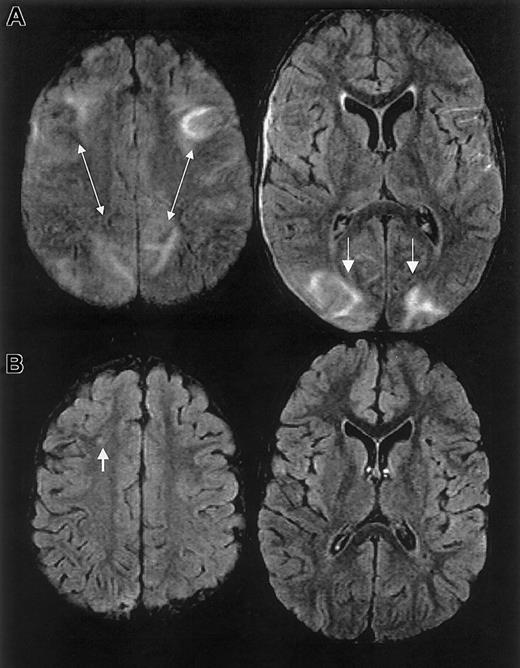

One year prior to ACS episode, the patient had a normal MRI study. MRI on hospital day 20 and 2.5 months following discharge revealed findings consistent with RPLS and silent cerebral ischemia (Figure 1).

MRI findings for case 1.

Multifocal areas of fluid-attenuated inversion recovery (FLAIR) T2-weighted signal abnormality in the subcortical white matter and overlying gray matter of the frontal, parietal, and occipital lobes (bottom).

One year prior to ACS episode, the patient had normal MRI/MRA and transcranial Doppler studies. MRI on day 10 and 1 month following discharge revealed RPLS with superimposed ischemic white matter changes (Figure 2).

MRI findings for case 2.

Multifocal areas of signal hyperintensity predominantly limited to the cortex of the posterior parietal and occipital lobes on FLAIR T2-weighted images, including punctate areas of abnormality in the deep, periventricular white matter of the right frontal lobe and of the cortex of the right medial parietal lobe. MRI done 1 month following discharge revealed punctate lesions in the frontal lobe, representing subacute to chronic ischemic changes, but resolution of the T2 hyperintense lesions in the posterior distribution.